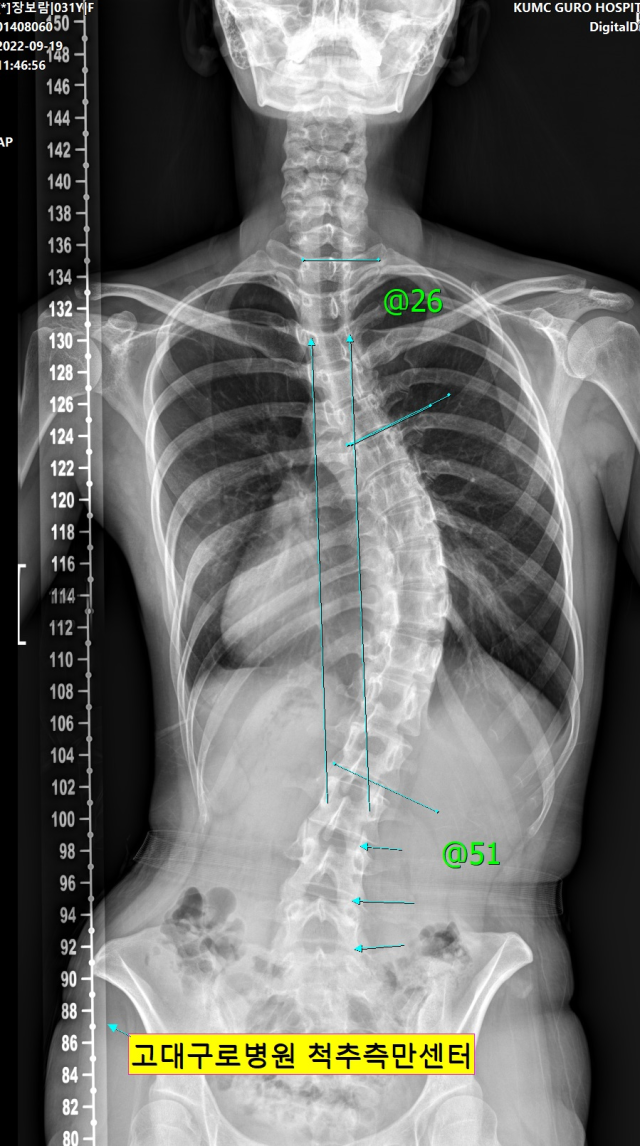

▲50도 넘는 만곡도를 보이는 장보람 씨의 척추. ⓒ장보람 제공 |

장 씨는 현재 만곡도가 50도 넘는 고도 척추측만증을 갖고 있다. 이는 지체장애인 판정을 받을 수 있을 정도로 심각한 장애다. 남성의 경우 병역판정검사에서 5급 판정을 받아 현역에서 제외될 수 있다. 장 씨는 유년 시절 특발성 척추측만증(원인을 알 수 없이 발생한 척추측만증) 진단을 받은 뒤 정기검진과 교정기, 운동을 장기간 병행했음에도 증세 악화를 막을 수 없었다.